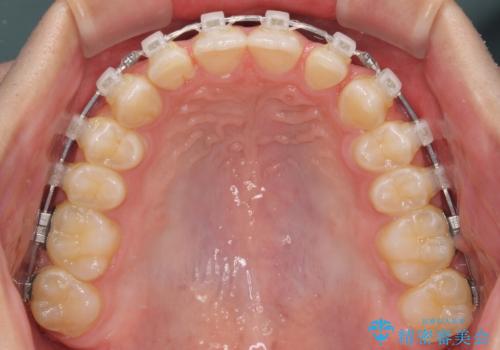

- クリアブラケット

下顎前歯が全て隠れてしまうほどの深い咬合で、左右の奥歯は1歯対1歯で咬み合う状態でした。

前方に移動している上顎臼歯を補助装置にて遠心移動させることで1歯対2歯の臼歯咬合を目指し、同時に深い咬合を改善していくこととしました。

このような咬み合わせの場合、治療期間は2年以上がかかることが一般的で、3年程度かかることもありえるケースです。

強く深い咬み合わせにより下顎装置は頻繁に脱離するため、治療期間が長くなりますが、予定通りに終了させることができました。